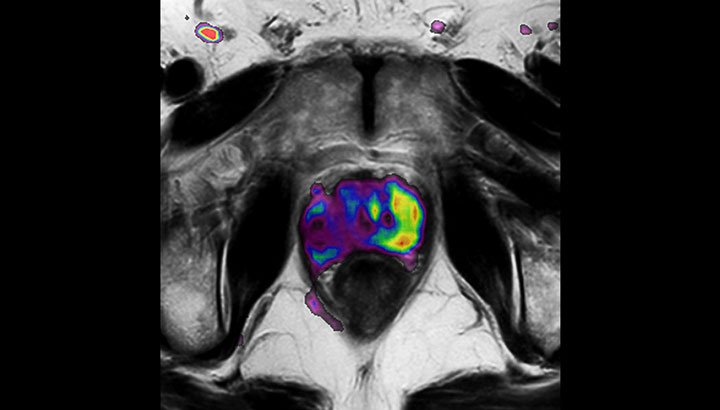

MRIは軟部組織の視覚化に優れており、幅広い画像コントラストに対応します。これにより、MRIは腫瘍の境界をより正確に描出できる強力なツールとなっています。放射線治療プロセスにおいて、標的体積の描出における不確実性が指摘されることがあります**。ターゲットとその近傍のリスク臓器をより良好に可視化することは、標的体積の描出を改善するための重要な因子です。また、MRIの役割は機能的イメージングにより広がりつつあり、ターゲットの評価と治療反応の両方の情報を提供します。

さまざまなコントラスト情報の利用により、腫瘍の特徴や腫瘍の範囲について有益な情報が得られます。また、追加照射のストラテジーへの情報提供にもなります。

解剖学的情報に加え、MRIは腫瘍の検出と描出、および治療反応のモニタリングに有益な機能的情報提供することができます。

例えば、拡散強調画像(DWI)は腫瘍の水分子の移動(拡散)の制限を示すほか、リンパ節の識別にも用いられます。また、組織や病変部の見かけの拡散係数(ADC)の変化は、放射線治療に対する腫瘍の反応を予測するのに役立つ知見を提供することができます。